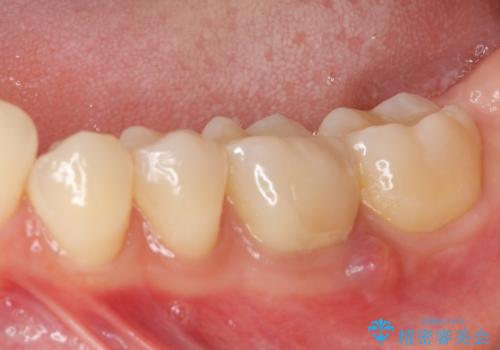

- 近医にてセラミックを装着した左下の奥歯に痛みが続いたとのことで来院された患者様です。

診査の結果、既に歯の神経は失活していたおり、排膿路が認められ、叩いたり触ったりしたときの痛みも確認されました。

根管治療を行った後にオールセラミッククラウンにて補綴することとしました。

初回の治療後には歯肉に認められた排膿の出口などの症状は消えていました。

補綴後6ヶ月経過しレントゲンを撮影したところ、遠心の歯根付近の病変が消失していることが確認できました。